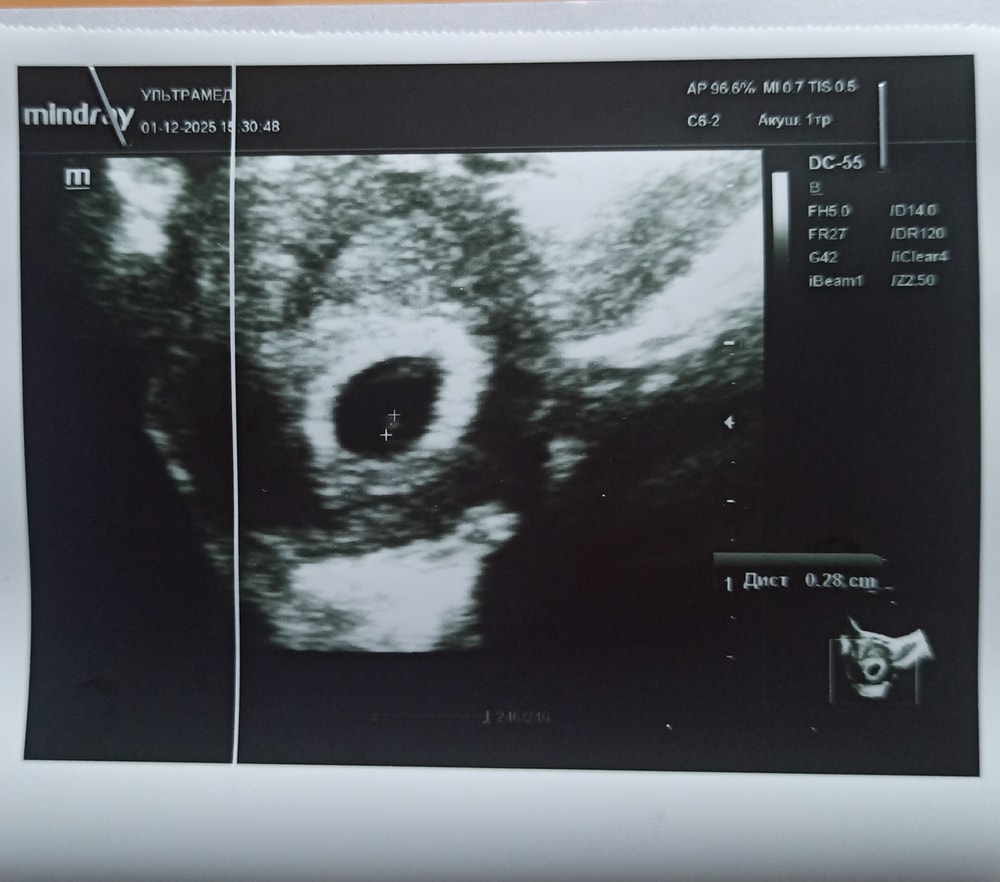

Сегодня была на УЗИ🙏 Ииииии я увидела практически сразу как пульсировало маленькое сердечко😍🥺🙏

П.я - 18 мм.

Ктр-3 мм.

Желточный мешочек +.

Шейка 31 мм.